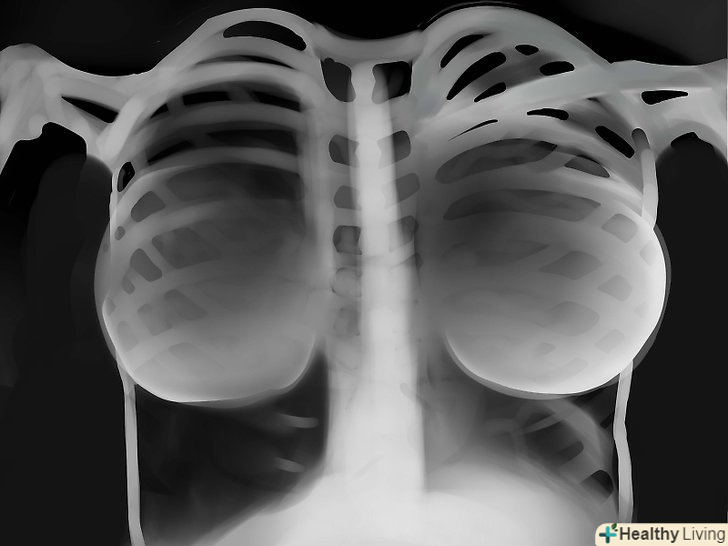

Інструменти.всі трубки, водії ритму, хірургічні затискачі, дренажі, імпланти - все це треба знайти.